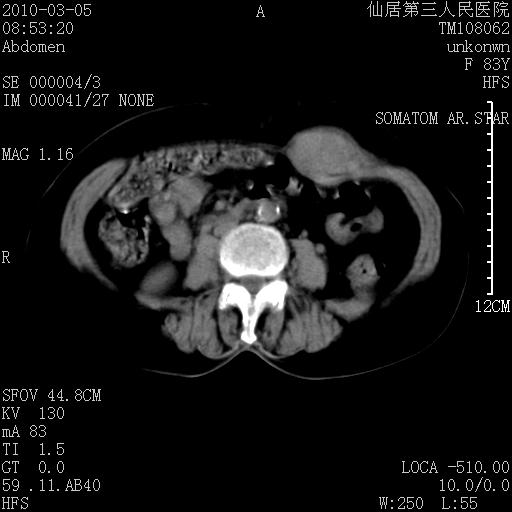

标题: CT24879:腹直肌病变。在线等。

女性,83y,腹痛一周。

增强看看,mfh可能性大,次之可考虑血肿、bfh、转移瘤、神经纤维瘤、侵袭性韧带样纤维瘤等。肝内钙化灶,右肾结石。